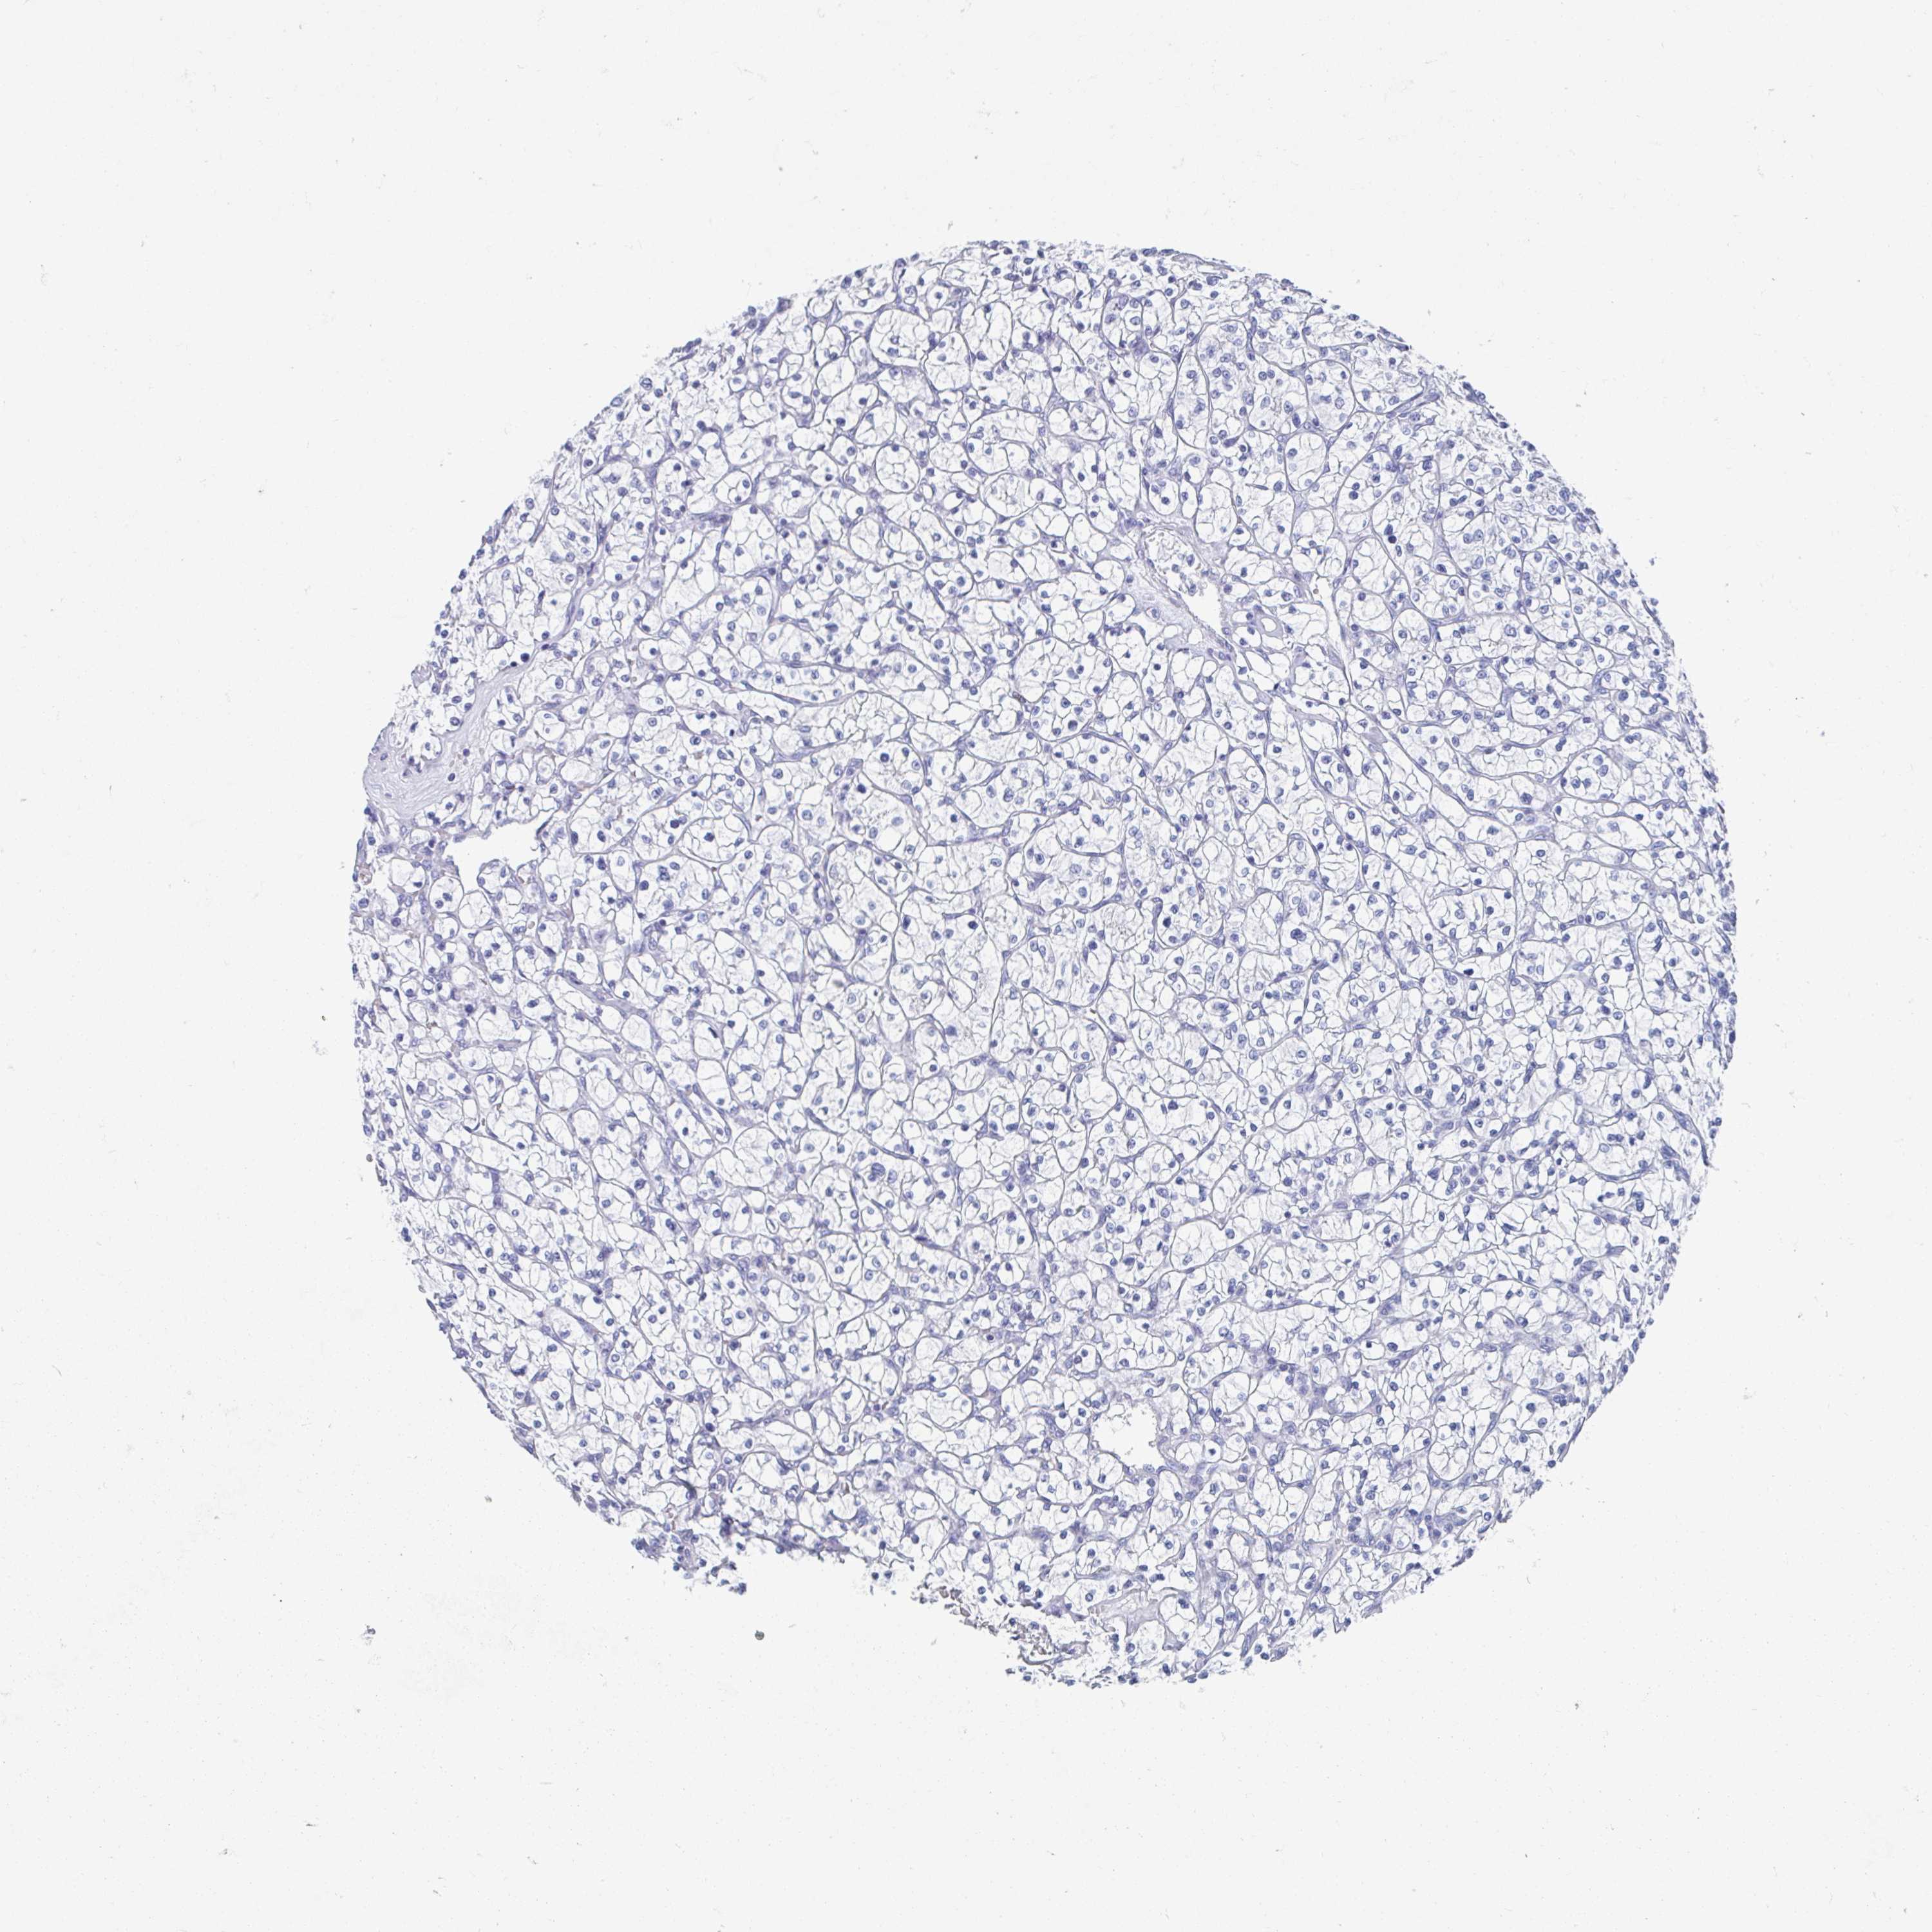

TCGA RNA samplesi

RNA-seq data is reported as average FPKM (number Fragments Per Kilobase of exon per Million reads), generated by the The Cancer Genome Atlas (TCGA) .

Normal distribution across the dataset is visualized with box plots, shown as median and 25th and 75th percentiles. Points are displayed as outliers if they are above or below 1.5 times the interquartile range. FPKM values of the individual samples are presented next to the box plot.

Average pTPM 0.0

Number of samples 521